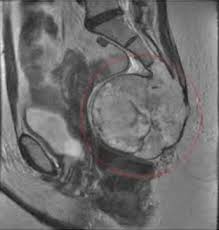

Спитаєте, що робити, якщо виникли проблеми з куприком? Це може бути біль, травма або навіть пухлина. Як читач, ви повинні знати: це серйозні речі.

- Пухлина: рідко, але можливо.